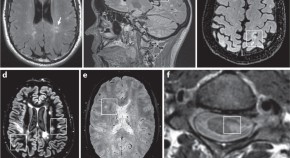

Myelin oligodendrocyte glycoprotein antibody-associated disease is an immune-mediated demyelinating disease that is distinct from multiple sclerosis but shares some of its characteristics. This Expert Recommendation, based on a Magnetic Resonance Imaging in MS workshop, proposes a diagnostic algorithm for the differential diagnosis of myelin oligodendrocyte glycoprotein antibody-associated disease and multiple sclerosis, using serological, imaging and clinical features.